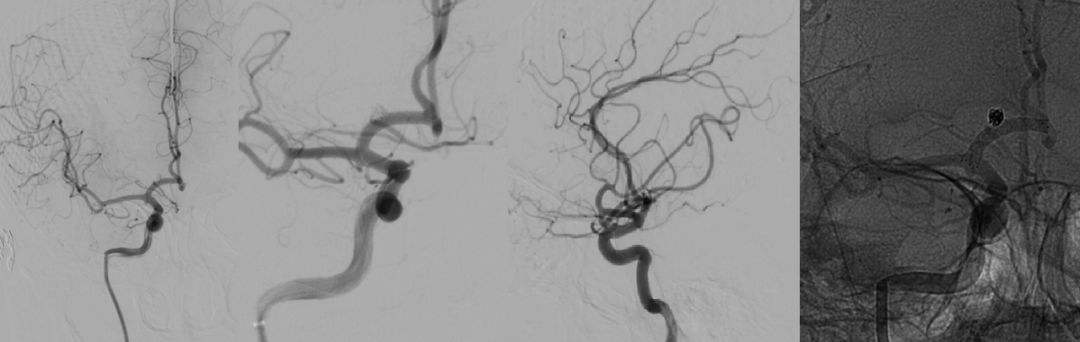

图1 术前造影显示右侧颈内动脉A1段动脉瘤,伴子瘤样改变,返动脉发自瘤体

图2 左侧颈内动脉压颈造影见左侧A1段缺如

图3 三维旋转见右侧A1、A2角度较大

图7 术后造影见动脉瘤不显影,分支血管及载瘤动脉通畅,支架位置可